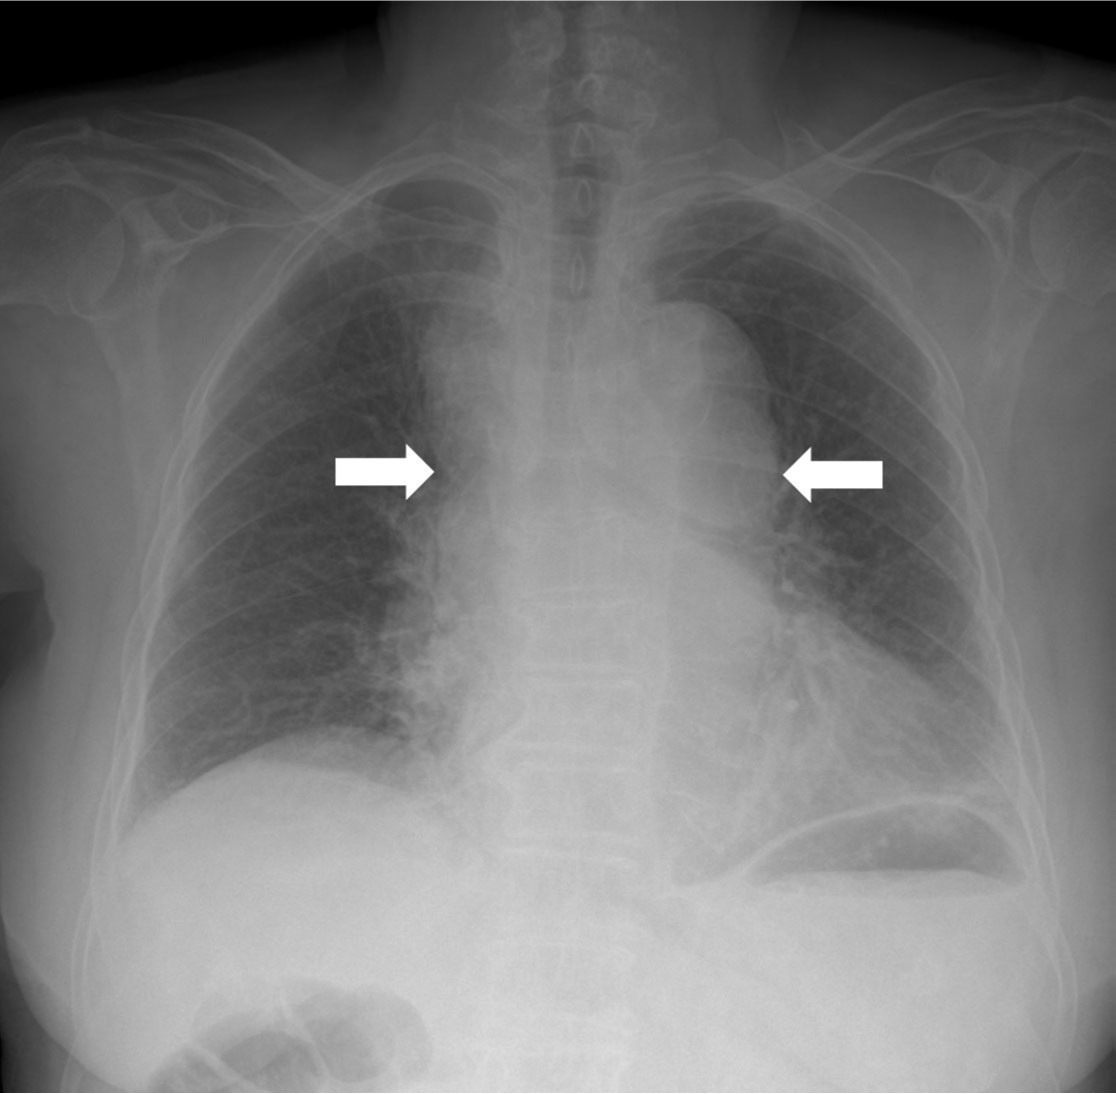

Chest radiograph에서 상부 종격동 비대를 보이고 있었고 좁아진 기관지 내강이 관찰됨(Fig. 1). CT angiography에서 후종격동에 거대한 혈종이 있으며, 이 혈종 내부로 조영제가 유출되고 있음(Fig. 2A). 조영제 유출은 하행 대동맥에서 기시하는 우기관지동맥과 연결됨(Fig. 2B).

Fig. 1.

Fig. 1. Chest radiograph shows mediastinal widening (arrows).